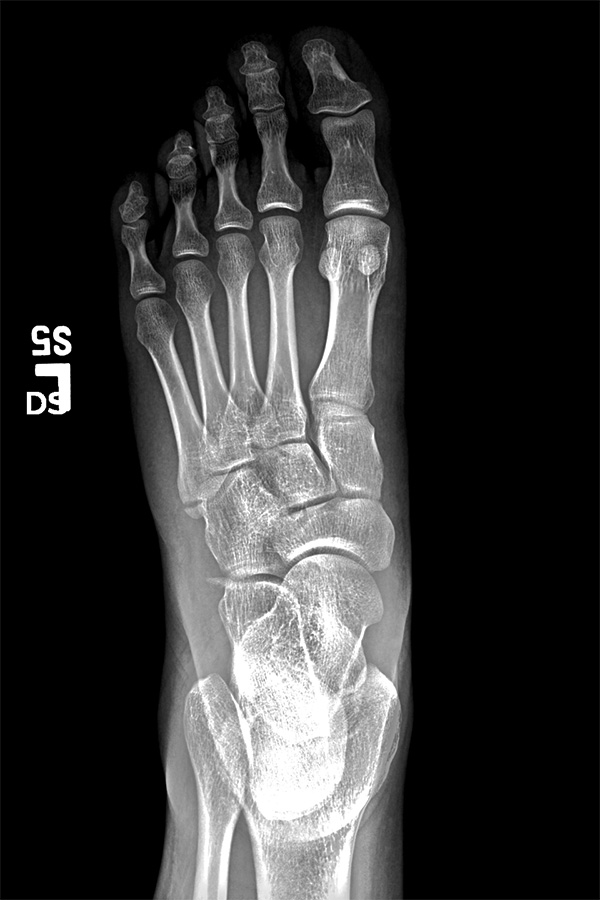

i had nothing to lose and was curious to get my hands on my broken foot x-rays from last year 2 years ago, so i went to the sub-basement of the bigelow building. i wasn't sure if i could get it today, and i wasn't sure if i had to pay. the man who helped me said he'd put everything onto a disc, and that he could do it while i waited. what i thought would be a quick wait ended up being almost 45 minutes. the big hold up were the MRI scans, which i already had a copy. was he downloading the images via 1990's modem technology? i also learned that if you request the images for personal use then you'd have to pay, but it's not seriously enforced, and if you just make up a doctor, you can get everything for free (they give you the disc anyway, they don't mail it out).